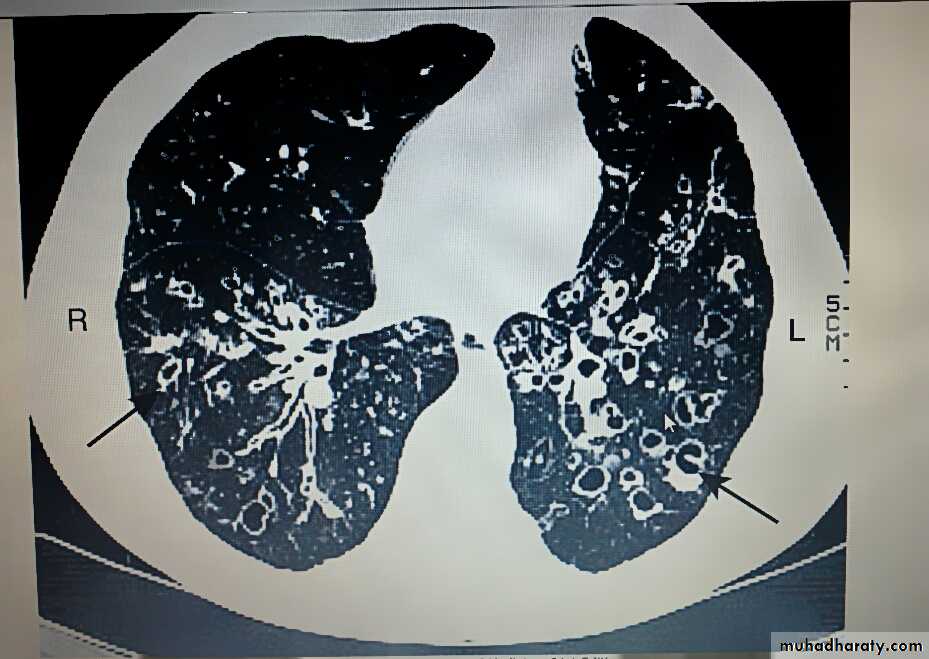

• 2)Radiological examination

• Bronchiectasis, unless very gross, is not usually apparent on a chest X-ray. In advanced disease, thickened airway walls, cystic bronchiectatic spaces, and associated areas of pneumonic consolidation or collapse may be visible. CT is much more sensitive, and shows thickened dilated airways.